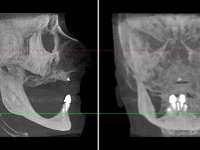

After clinical and radiological evaluation several rehabilitation plans were discussed with the patient. It was decided to extract the remaining lower teeth and do an overdenture retained by two dental implants with the locator attachement system to achieve a better retention and stabilization of the lower denture.

Two dental implants were planned in the CBCT scan, in the area of the inferior canines. The dental extractions were performed and, simultaneously, the alveolar crest was flattened and the implants were placed. Three issues were considered while implant placement: parallelism of the axis, same height of the implant’s neck, and same position in the coronal plan. This 3D insertion is essential to have a good retention of the overdenture in the future. Patient’s removable denture was fixed in the dental lab, to include the extracted teeth, and a soft-tissue relining was done over the healing abutments. After the osseo-integration period, a first impression was done with an open-tray and a doble-mix technique. This dental impression allowed the production of screwed wax-rims and an individual tray for a functional impression. A second impression, final, was done with an individual tray with a monophasic silicone. The occlusal wax-rims were correct in the mouth according to the full denture guidelines. Special care was taken with the occlusal vertical dimension and the support in the soft-tissues. A silicone bite registration material was used to better defined the intermaxillary relations. Teeth set-up was done in the dental lab with the selected tooth color. Due to the fact that the base was screwed to the dental implants, the teeth set-up was functionally evaluated in the mouth. Another silicone bite registration material was used to allow final occlusal adjustments. Finally, the locators were screwed and the retention nylons were selected according to the patient needs.